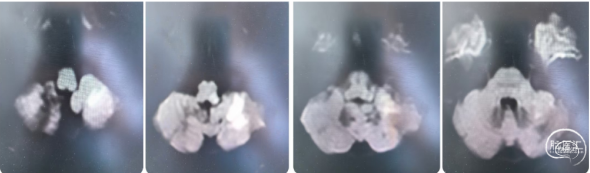

病史:患者入院2.5小时前休息时突发言语不利,难以与人交流,能理解他人言,右侧肢体无力,口角歪斜,行走、持物不能;双眼向左侧凝视。于11:30至我院急诊就诊,急查头颅CT未见颅内出血;CTA+CTP示左侧大脑中动脉M3闭塞,存在缺血半暗带。

术前CTA

手术过程

1、行右侧股动脉穿刺并置入8F动脉鞘成功。造影发现左侧大脑中动脉M3段以

远显影欠佳。正位不清晰,斜位清晰可见M3闭塞。

2、5F 125cm 中间导管抽吸:

泥鳅导丝引导8F导引导管至左侧颈内动脉C1远端平直处建立通路,微导丝引导微导管及5F 125cm 中间导管到达左侧大脑中动脉M3闭塞段近端。

近端使用60mL注射器手动抽吸两次,未见血栓取出。可能为导管未能接触血栓。

注意: 6F 125cm 中间导管到达大脑中动脉M1段; 5F 125cm中间导管到达大脑中动脉M2分叉以远。

3、换用3MAX 抽吸导管通路组合:

8F MPA+3MAX抽吸导管+微导丝,抽吸两次后栓子逃逸至远端分叉部。

5、 再次跟进3MAX抽吸一次,完全再通。

术后即刻复查XperCT未见出血。

术后第二天查看患者:神志清楚,应答切题,构音欠清晰。右上肢肌力2级,右下肢肌力3级。NIHSS评分8分。